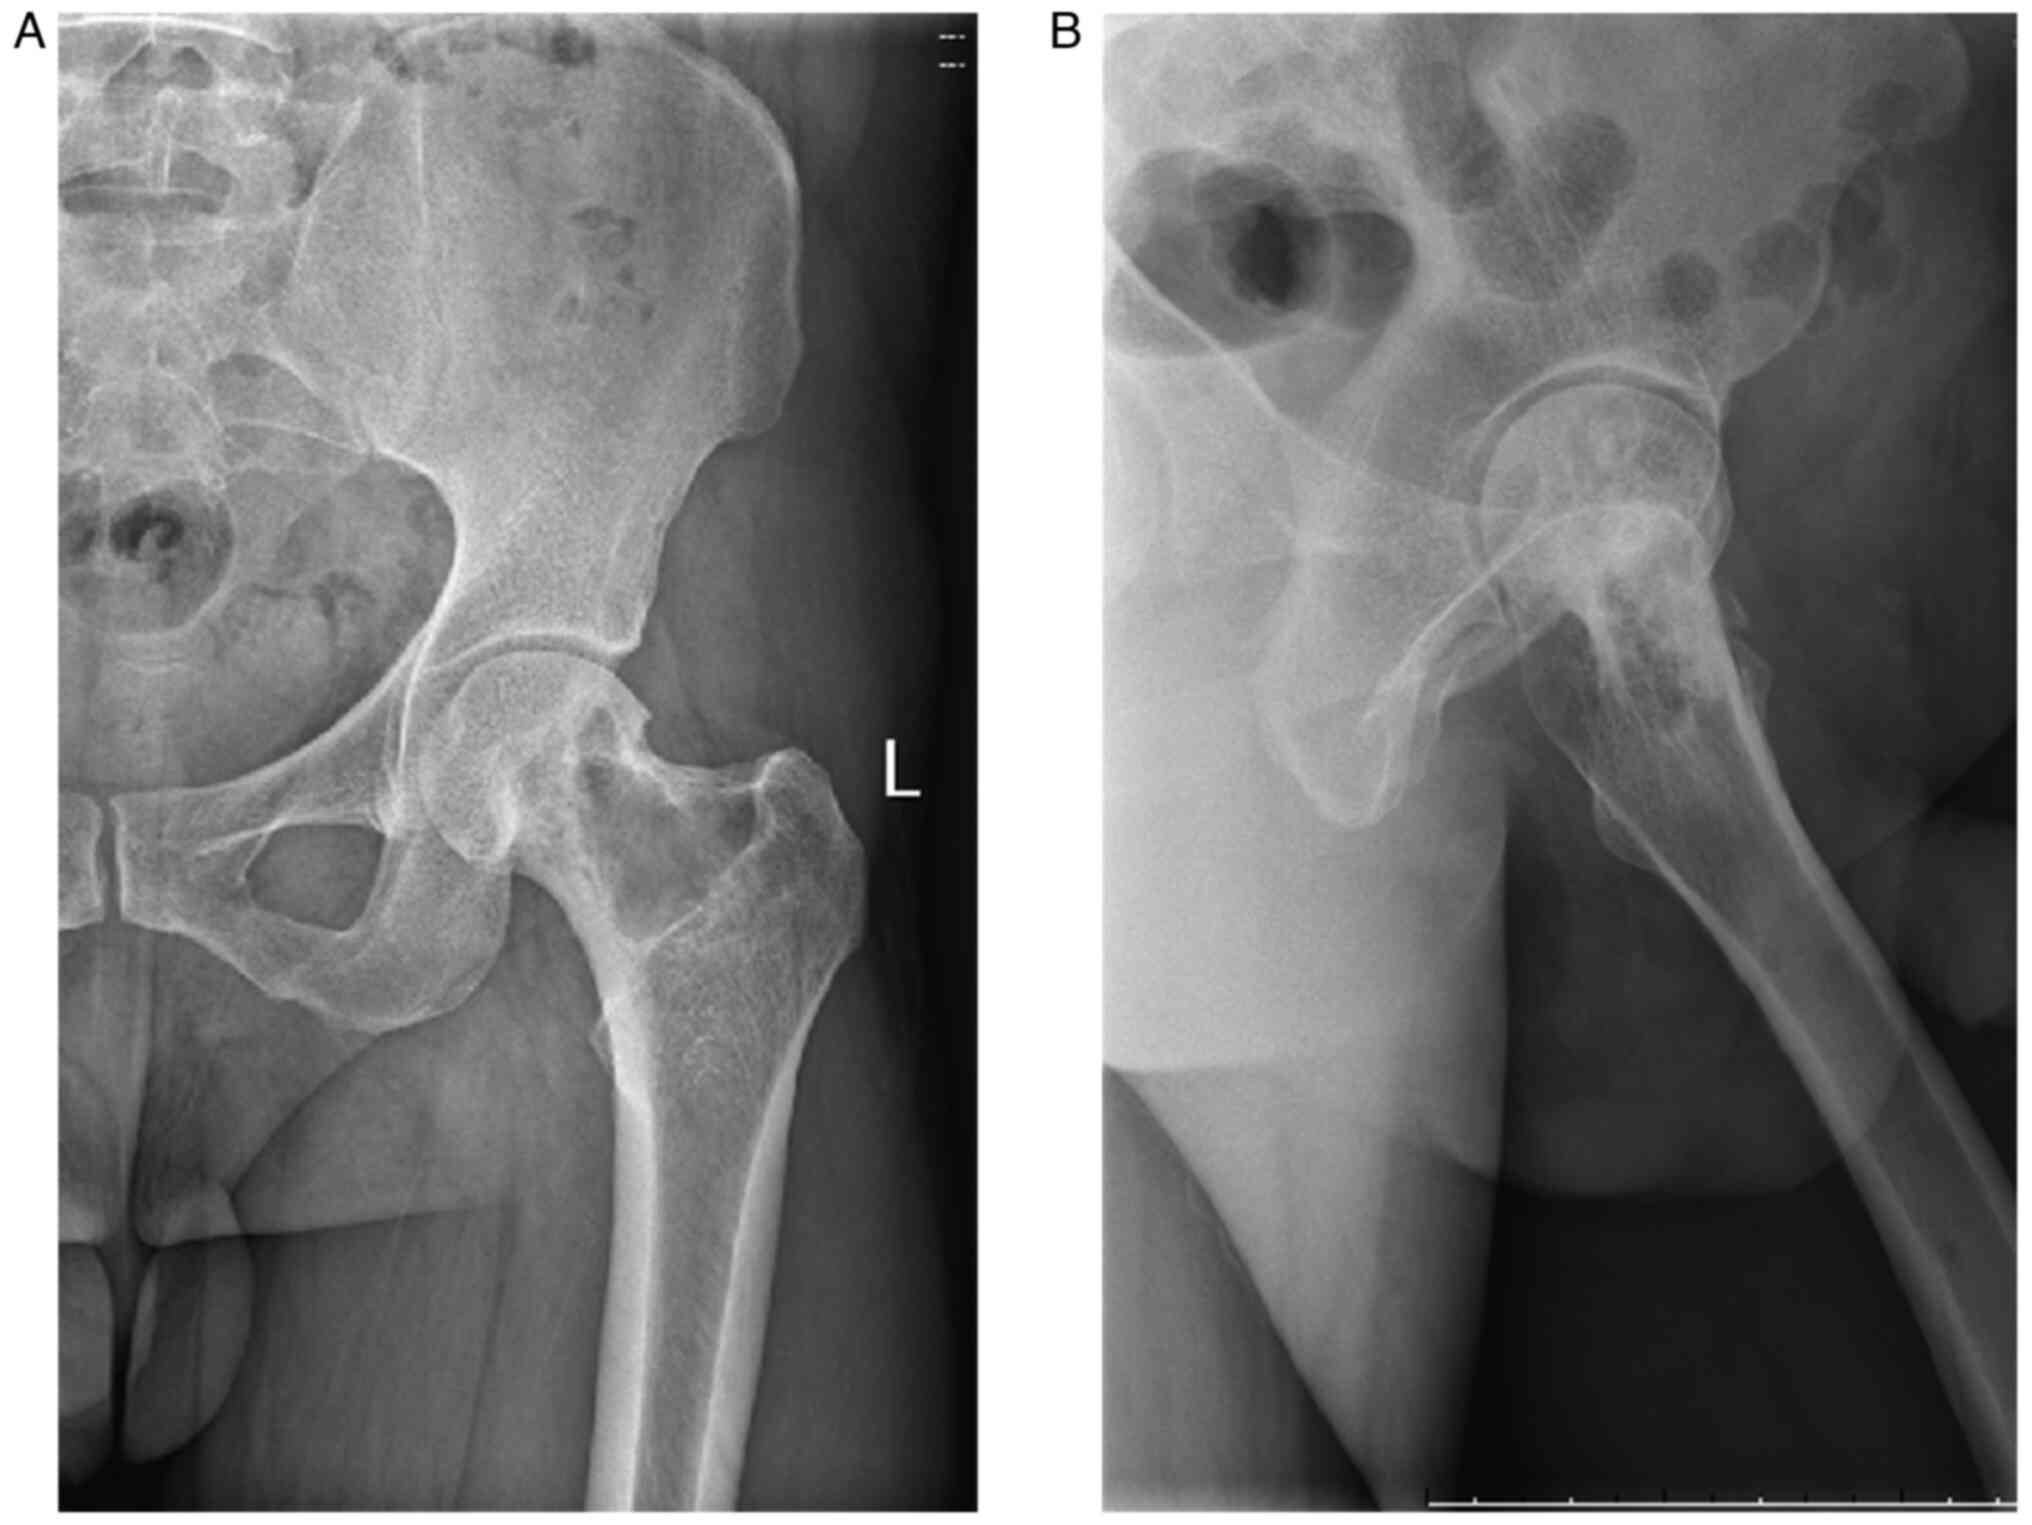

Malignant transformation of an aneurysmal bone cyst of the femoral neck: A case report

Aneurysmal bone cyst (ABC) is a benign, distending, osteolytic and locally aggressive bone tumor that is mostly associated with trauma. Approximately 1% of bone tumors are ABCs, which are most prevalent in adolescents and are usually detected in the spine and long tubular bones. The diagnosis of ABC mainly relies on histopathology, malignant transformation is rare, and the chance of malignancy increases if there are multiple recurrences. Due to the rarity of reports of malignant transformation of ABCs into osteosarcoma, there is still considerable debate on the appropriate treatment strategy. The current paper presents a case of aneurysmal bone cyst malignant to osteosarcoma and the therapeutic measures to provide expertise for the diagnosis and treatment of ABCs that are malignant to osteosarcoma.